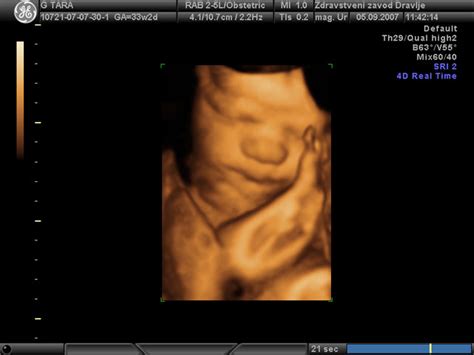

V 32. tednu nosečnosti ultrazvočni pregledi postanejo ključno orodje za spremljanje rasti in razvoja ploda. Meritve, kot so premer glavice (BPD), obseg glavice (HC), obseg trebuščka (AC) in dolžina stegnenice (Femur/FL), omogočajo oceno telesne teže ploda (EFW - Estimated Fetal Weight). Vendar pa te številke pogosto vzbujajo skrb, če jih nosečnice ne razumejo v celoti.

Primer, kjer nosečnica v 32. tednu nosečnosti prejme naslednje meritve: BPD 88,2 mm, OFD 122,3 mm, HC 339,9 mm, AC 315,0 mm, Femur 66,3 mm, Hc/Ac 1,08, EFW 2,690 g. Te meritve so bile interpretirane kot normalne za nosečnost, pri čemer je bil plod ocenjen na 2700 g. Kljub temu se pojavi vprašanje glede potencialne velikosti otroka ob terminu in možnih težav med porodom, še posebej, ker gre za prvorodko.